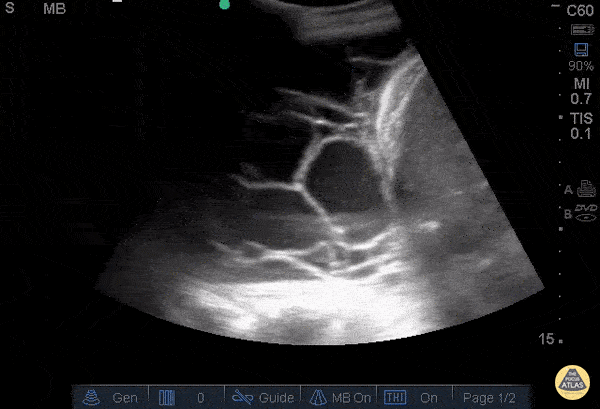

Lignes B pathologiques. Ce GIF montre la présence de nombreuses lignes B (plus de 3 par espace intercostal). Ces artéfacts verticaux, "en queue de comète", partent de la ligne pleurale et s'étendent jusqu'au bas de l'écran sans s'atténuer, effaçant les lignes A. Ils signent une perte d'aération pulmonaire

Présence d’au moins trois lignes B par espace intercostal, s’étendant jusqu’au fond de l’écran, effaçant les lignes A et se déplaçant avec le glissement pleural.

- Syndrome interstitiel (lignes B) → excès de liquide ou épaississement interstitiel.